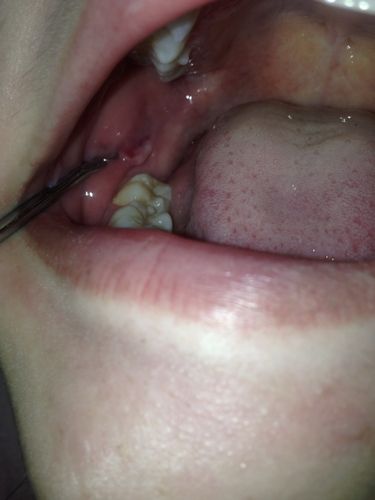

溃疡愈合期的“肉芽组织”(最常见)

这是最有可能的情况,通常无需过度担心。

- 成因:当口腔溃疡(特别是较深的溃疡)开始愈合时,身体会启动修复机制,在溃疡的基底,会生长出新的血管和结缔组织,形成粉红色或淡红色的、柔软的、微微隆起的“肉芽组织”,它的作用是填补溃疡缺损,为上皮细胞的生长提供“脚手架”。

- 特点:

- 颜色:粉红色或鲜红色,与周围黏膜颜色相似。

- 质地:柔软,触感不硬。

- 感觉:可能没有明显疼痛,或者只有轻微的触痛,原有的剧烈疼痛感已经减轻。

- 变化:随着时间推移,它会逐渐变平,最终被正常的口腔黏膜覆盖,完全愈合。